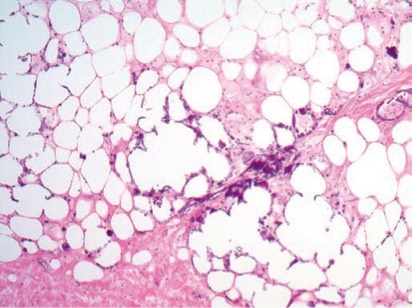

948. У пациента с почечной недостаточностью, длительно находящегося на диализе и принимающего антациды на основе алюминия, наблюдают множественные поражения почек, легких и кожи, выполнена биопсия, патологический процесс представлен